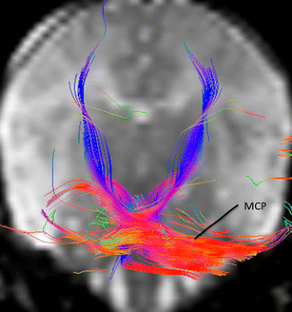

Fig. 2